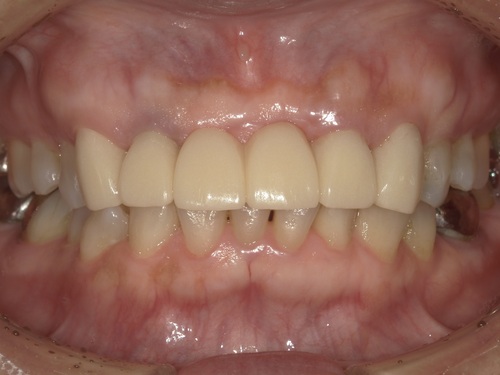

⑦セット

型取りから2週間ほどでジルコニアセラミックブリッジが完成してきました。

適合・色合い・噛み合わせに問題がないことを確認し、歯科用セメントでしっかりとセットしました。術前と比較して色も自然でとても美しい仕上がりかと思います。

初診時にはインプラント治療にするかブリッジ治療にするか大変悩まれておりましたが、綺麗なブリッジが入って、患者様は今回の治療に大変満足されております。また保険外治療で高額な治療とはなりましたが、とても綺麗な歯が入ったと『ジルコニアセラミックにして良かった』とおっしゃられておりました。